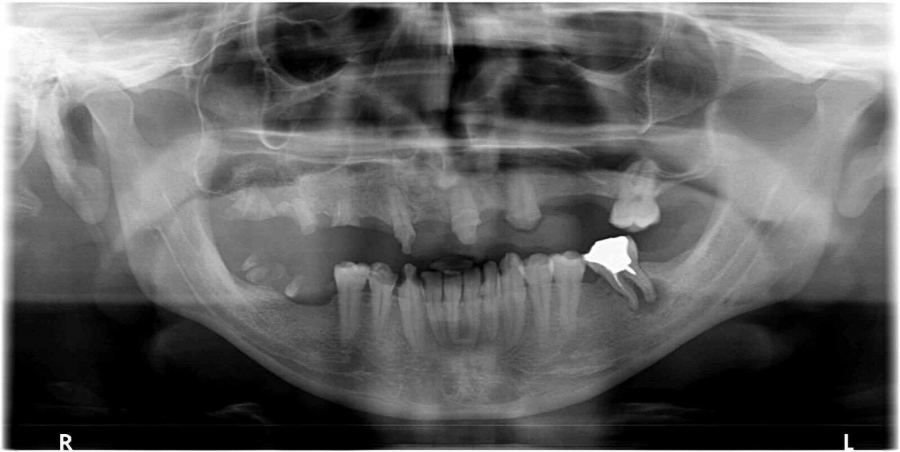

تصوير بانوراما للأسنان في عياده الدكتور اشرف كبها / برطعةتصوير بانوراما للأسنان في عياده الدكتور اشرف كبها / برطعةتصوير ديجيتالي ،للاستفسار الاتصال على رقم 0544304540 ورقم العياده 042465568 13/11/2017 22:16 7,821